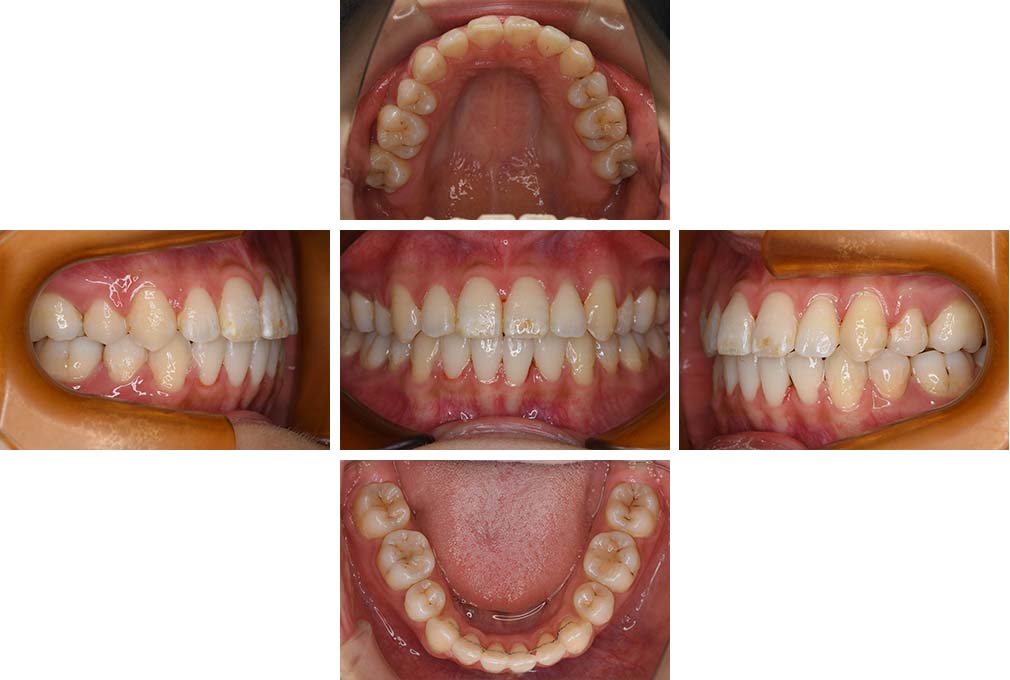

CASE:03

上下顎前突

初診時年齢 18歳4か月

性別 男性

治療費の目安 105万円程度(治療開始時)

歯列の乱れは著しくなく上顎右側側切歯が捻転し口蓋側へ転位していた。また、問診の中で患者さんから最も重視する治療結果として口元の突出の改善の申出があった。下顎が後退した上顎前突傾向ではあったが著しいものではなかった。上下顎前突と診断し上下顎小臼歯抜歯を行っていただき、上下顎舌側マルチブラケット装置を使用して、矯正用アンカースクリューを併用して動的治療を行った。上下顎前歯の後退を十分行い口元の突出感も改善した。治療後10年1か月の来院時には口元の突出感が再発することもなく、下顎前歯の少しの唇舌的なずれはあったが歯列は安定していた。動的治療期間2年2ヵ月間。

治療前

18歳4ヵ月

治療後

動的治療期間2年2カ月間

20歳10か月

10年経過

動的治療終了後10年1カ月

30歳11か月